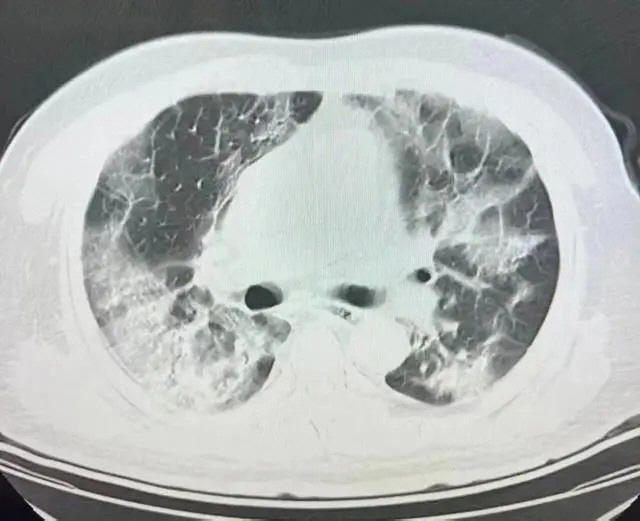

자외선 차단제 뿌린 7세 소녀, 하루 만에 폐가 하얗게 변해

중국에서 스프레이형 자외선 차단제를 뿌린 7세 소녀의 폐가 하얗게 변해 충격을 주고 있다.

지무뉴스, 저장온라인 등 중국 매체들에 따르면, 최근 저장성 항저우시에 놀러 온 한한(7)은 외출하기 전 엄마의 자외선 차단제 스프레이를 받아 얼굴에 뿌렸다. 이후 기침이 시작됐는데 시간이 갈수록 점점 더 심해졌다.

부모는 딸을 호텔에서 쉬도록 했는데 잠시 호전되는 듯 했다가 더 심각한 상태를 보였다.

숨을 가쁘게 쉬는가 하면 점점 기운이 떨어지는 모습이었다.

서둘러 병원에 데려가 흉부 X선 검사를 받아보니 양쪽 폐 모두 거의 흰색으로 변한 상태였다.

혈액 검사에서는 백혈구가 상승한 것으로 나타났다.

소녀의 과거 병력을 들은 의료진은 자외선 차단제 스프레이 흡입으로 인한 급성 과민성 폐렴이라고 진단했다.

발병한 지 하루도 채 지나지 않아서 병변이 그토록 널리 퍼진 이유에 대해 담당 의사는 "급성 과민성 폐렴의 전형적인 증상"이라면서 "아이는 다른 사람들보다 더 심한 상태인데 제때 치료를 받지 않으면 심각한 폐렴, 호흡 부전 및 기타 상태로 악화돼 생명을 위협할 수 있다"고 설명했다.

병원에 입원한 아이는 집중 치료 48시간 만에 기침이 사라질 정도로 회복했다.

한 소아과 전문의는 "스프레이형 자외선 차단제를 아이의 머리와 얼굴에 직접 뿌리면 아이가 무심코 흡입할 수 있다"며 "일반적인 차단제에는 휘발성 유기 화합물과 같은 다양한 화학성분이 포함돼 있어 건강에 위험을 초래할 수 있다"고 경고했다. 이어 "특히 알레르기 비염, 아토피 피부염, 기관지 천식 등 기도 민감도가 높은 알레르기가 있는 어린이의 경우 심한 기침이나 쌕쌕거림 발작을 유발할 가능성이 높아 사용에 주의를 기울여야 한다"고 당부했다.